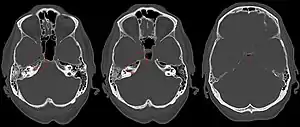

| Apicitis petrosa as seen in computed tomography | |

In persons with longstanding ear infection and typical symptoms, medical imaging such as CT or MRI of the head may show changes that confirm disease involvement of the petrous apex of temporal bone.